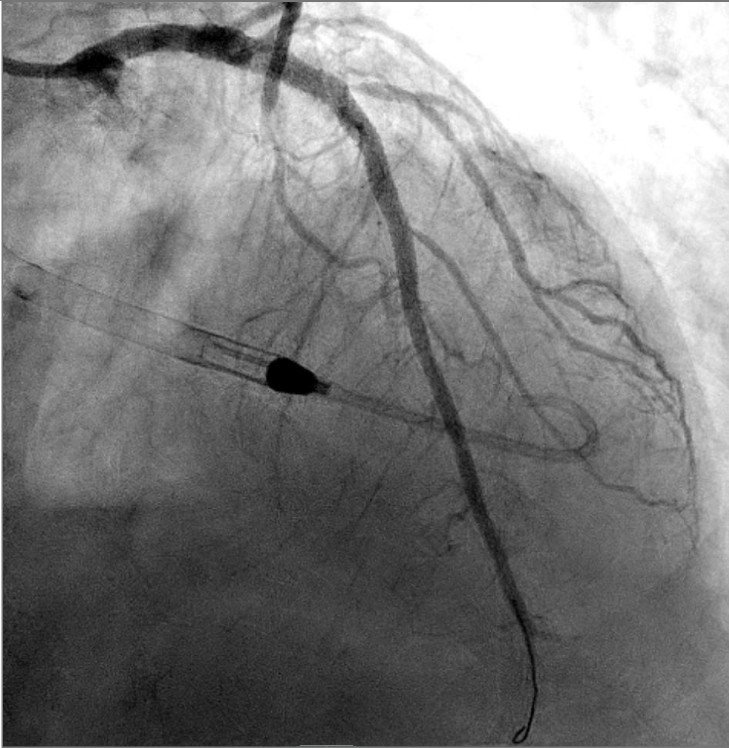

Angiogram showed culprit total occlusion of the proximal LAD.

Despite PCI, cardiogenic shock progressed on the cath lab table. Impella was used, and the patient was intubated for progressive respiratory failure.